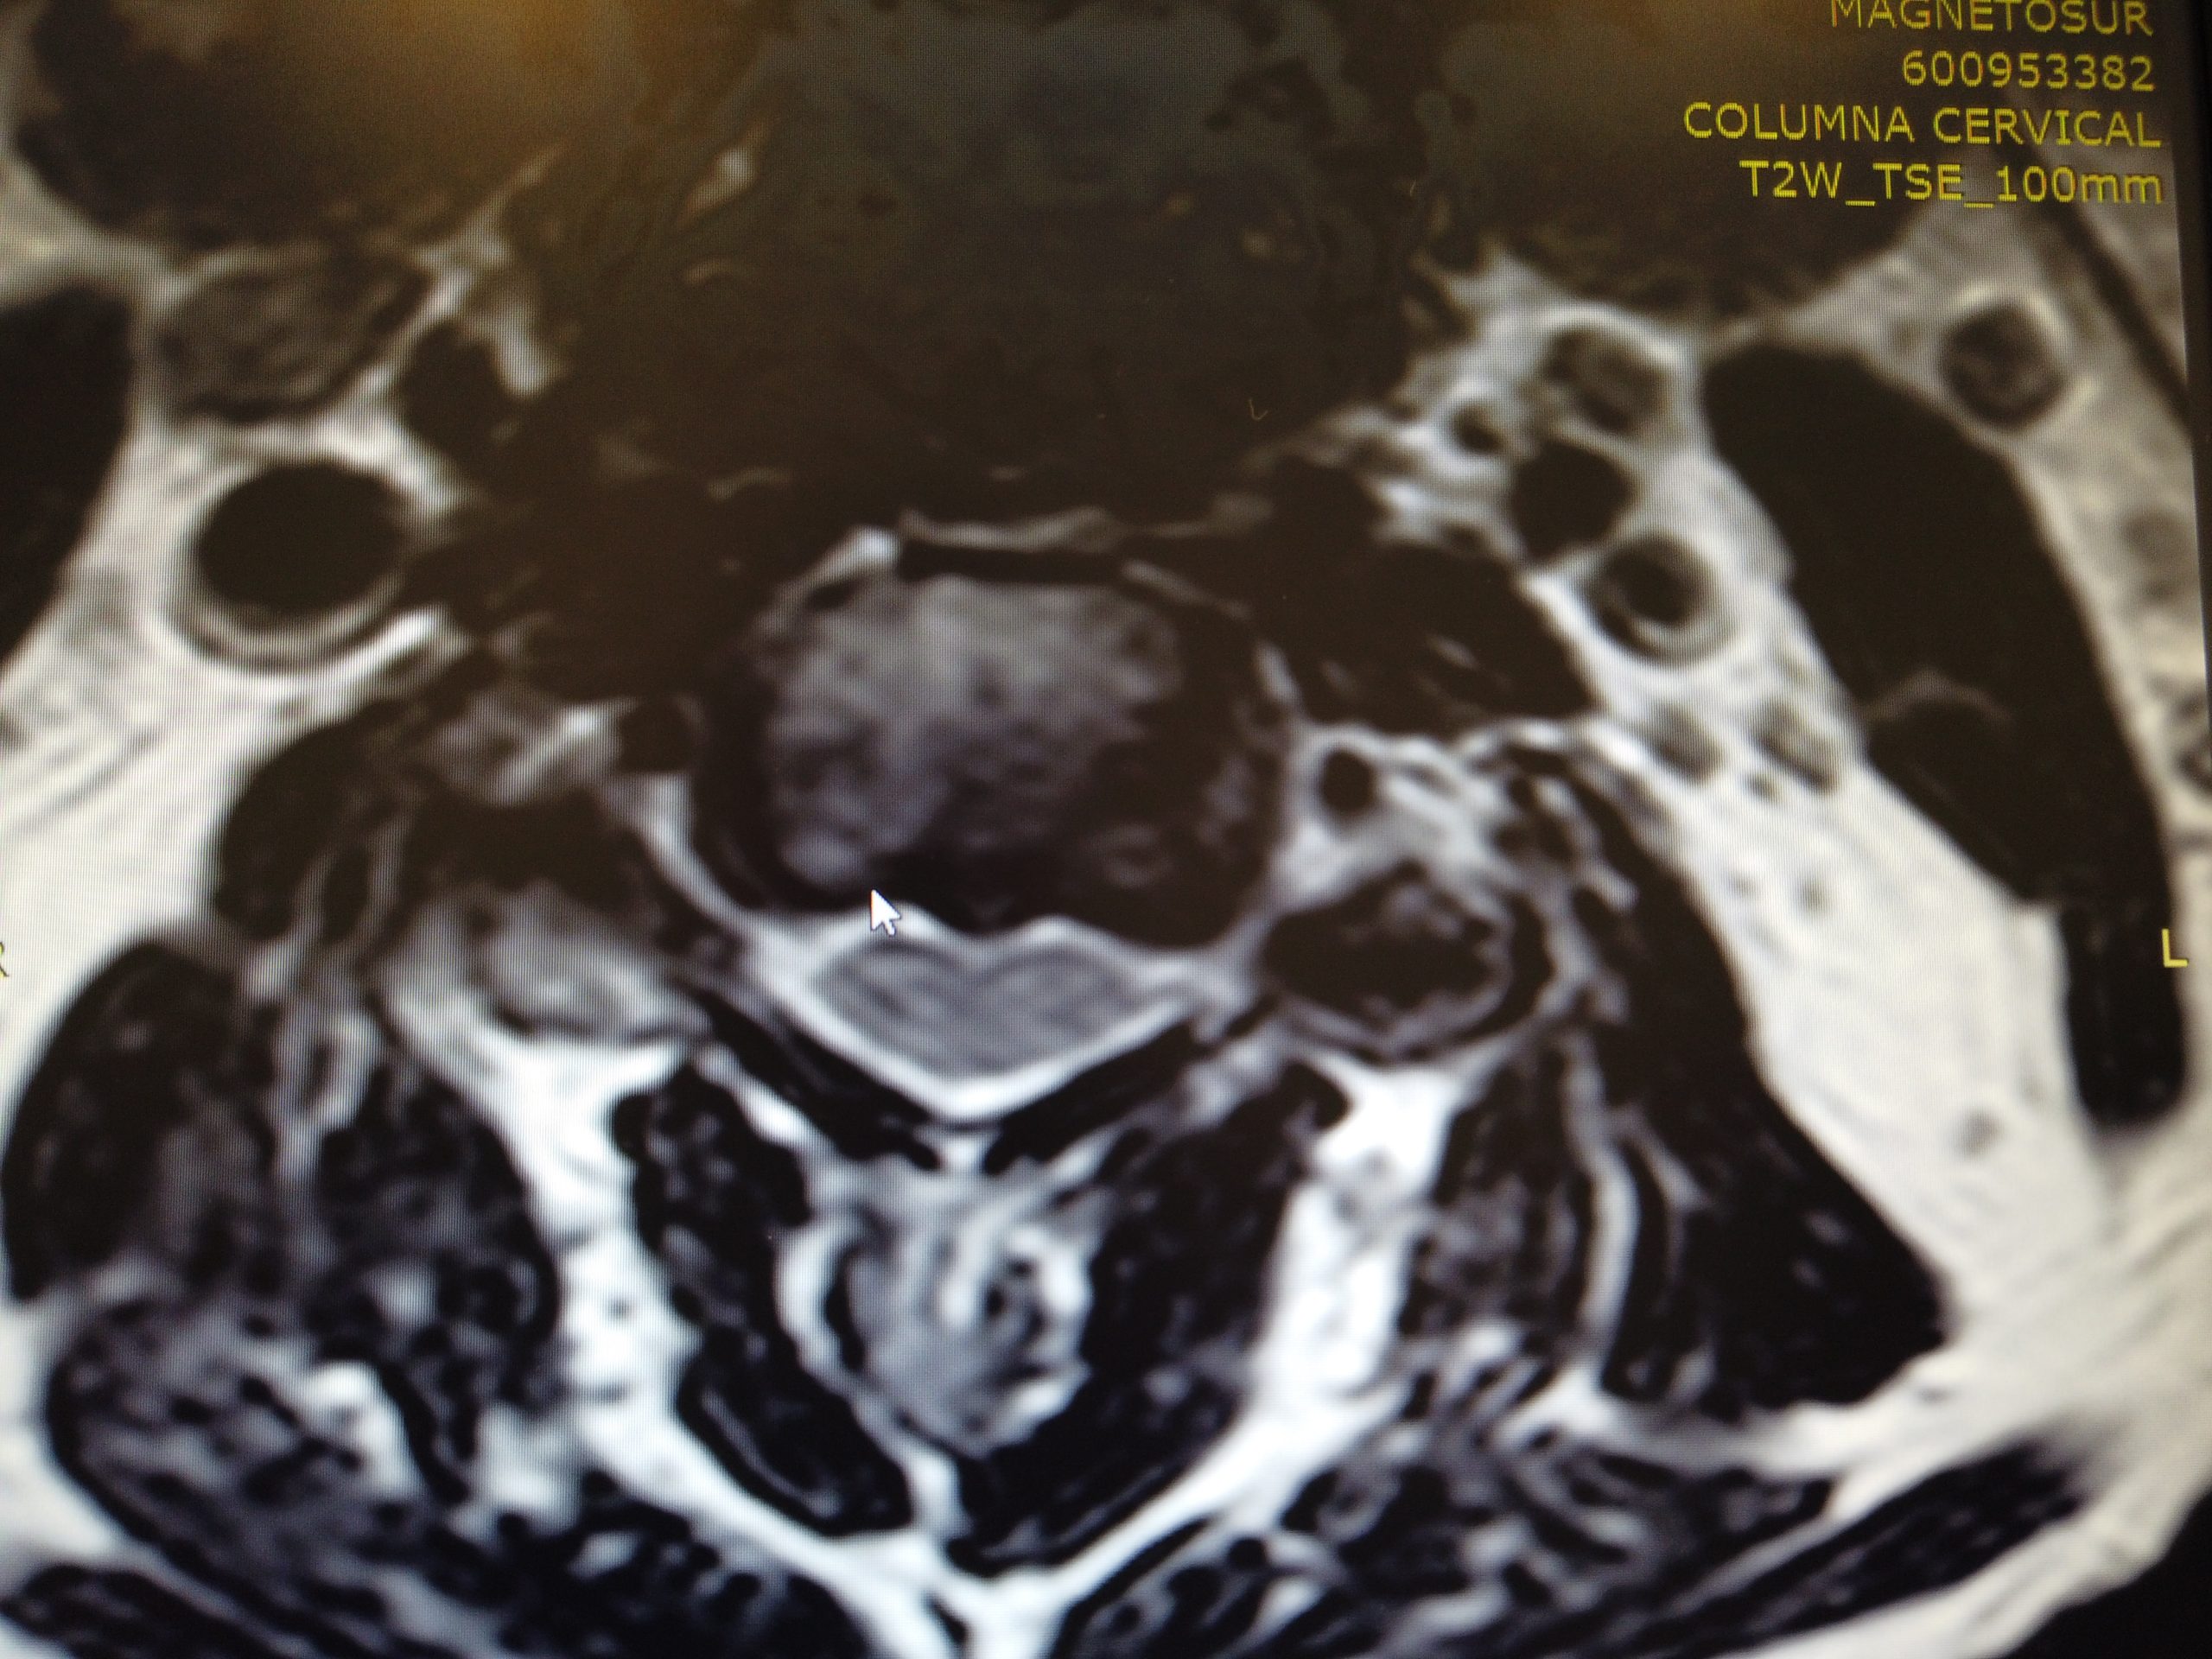

Caso de extrema dificultad en el que podemos ver a un paciente con dolor crónico cervical, parentesias MMSS y hormigueo en los miembros superiores.